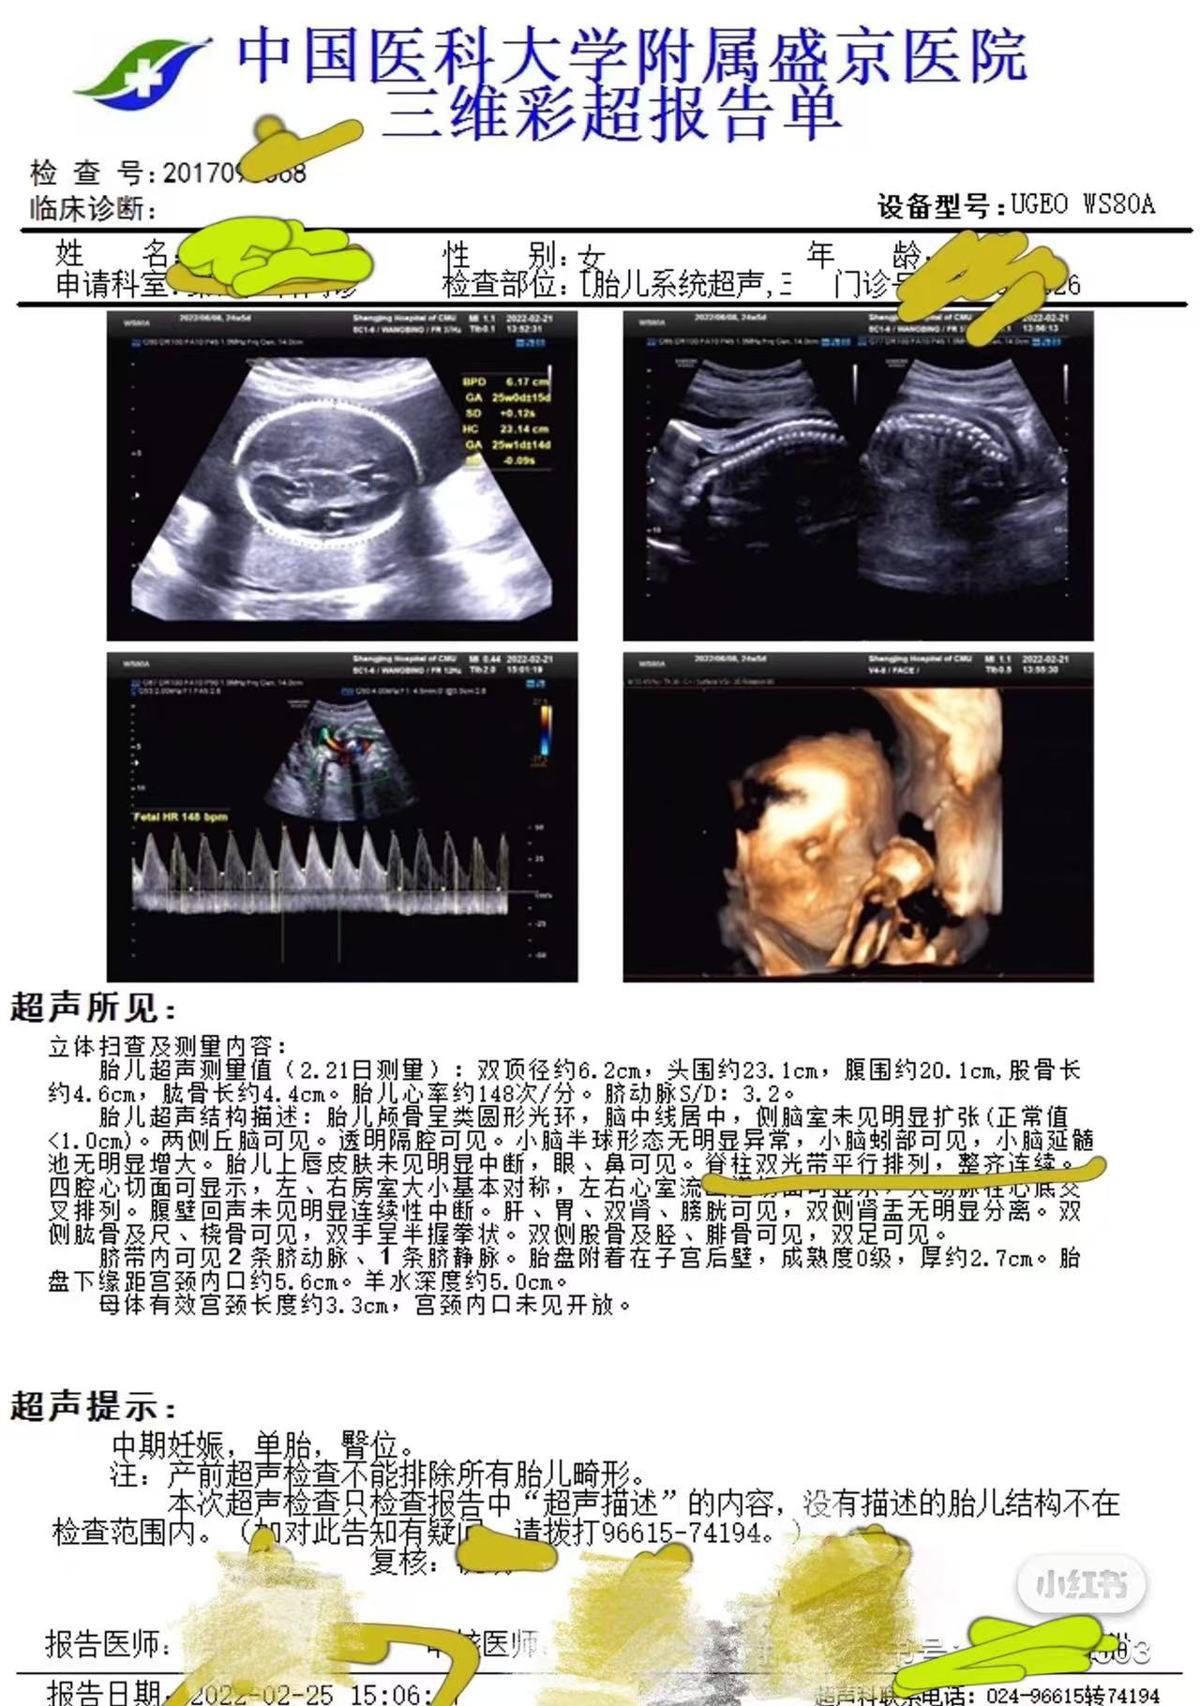

3月11日,高女士告诉极目新闻记者,2021年10月,她到盛京医院做了第一次产检并预约了后续的检查,2022年2月25日,她在盛京医院做了包括胎儿系统超声在内的大排畸检查,检查结果显示胎儿“脊柱双光带平行排列,整齐连续”,2022年6月15日,女儿出生。同年12月,女儿在核磁检查时被确诊脂肪脊髓脊膜膨出和椎管内脂肪瘤,即“脊柱裂”,“脊柱裂意味着女儿后期需要多次手术治疗,否则会足踝畸形、大小便失禁,严重的话甚至会导致下半身瘫痪。”

产前彩超显示胎儿脊柱正常(受访者供图)